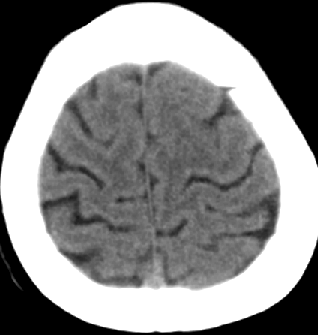

2013-8-2 CT

腰穿脑压240